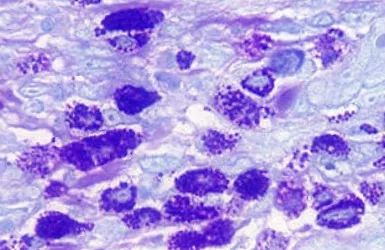

另外,嗜酸性肉芽肿还具有典型的组织细胞、嗜酸性粒细胞和多核巨细胞合并胶原变性的病灶点(就是一种病变啦),使用异染性染剂时,能观察到巨细胞增生(如图);

在口腔发生病变时,嗜酸性粒细胞可能存在于血液中,因而这种慢性病变就很少能检测到大量的嗜酸性粒细胞啦。